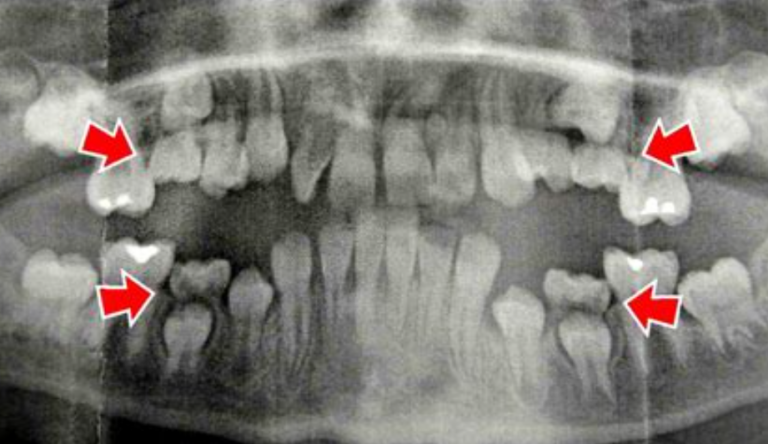

Czym jest elektrokoagulacja? Elektrokoagulacja to zabieg polegający na kontrolowanym wykorzystaniu prądu elektrycznego w celu zamknięcia naczyń krwionośnych oraz usunięcia zmienionych tkanek. W stomatologii metoda ta znajduje zastosowanie przede wszystkim w chirurgii i periodontologii. Stomatolog w nowoczesnej klinika stomatologiczna Kraków wykorzystuje…